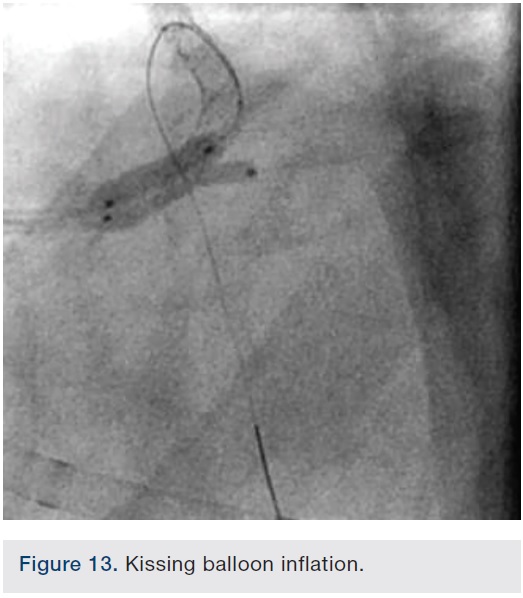

Following successful completion of the peripheral phase, it was felt that a 4-week period was necessary for the iliac stent to heal somewhat (especially since we planned to place a 14 French Cook sheath through it). We then moved on to the coronary phase of this procedure. Bilateral groins and the right wrist were prepared and draped in the usual sterile fashion. Using micropuncture technique with fluoroscopic verification of needle entry into the left CFA at the upper quadrant of the femoral head, a 6 French sheath was placed in the left CFA. The existing left femoral arterial sheath was removed, and the arteriotomy was pre-closed with a single Perclose device (Abbott Vascular). The arteriotomy was then serially dilated with 10, 12 and 14 French dilators, and a 14 French, 30 cm Cook sheath was placed successfully in the left common femoral artery. Following therapeutic anticoagulation with intravenous heparin, a regular J-wire and a 6 French pigtail catheter were used to cross the aortic valve, and the catheter was used to exchange the J wire for the 0.018-inch Platinum Plus wire (Boston Scientific). The Impella CP (3.5) percutaneous left ventricular assist device (LVAD) (Abiomed) was inserted into the left ventricle over the Platinum Plus wire (Figure 8). The Impella was then activated and good flows were verified. Right radial artery access was obtained and a PB 3.0 7.5 French sheathless guide system (Asahi Intecc) was used to engage the left main coronary artery. The LAD was wired uneventfully using a Runthrough wire (Terumo) via a 1.25 x 6 mm over-the-wire (OTW) Sprinter balloon (Medtronic). This was then exchanged for a Viper wire (CSI). Orbital atherectomy of the proximal LAD lesion was performed with excellent results (80,000 rpm x 4 passes, 120,000 rpm x 2 passes) (Figure 9). The LAD wire was then exchanged for a Runthrough wire and the left circumflex (LCX) was wired with a BMW wire. Following plaque modification with orbital atherectomy, predilation of LAD was performed with 3.0 x 20 mm Chocolate Balloon (QT Vascular Ltd) (15 atmospheres x 60 seconds and 15 atmospheres x 30 seconds) (Figure 10) with an excellent result and no dissection (Figure 11). A 3.5 x 38 mm Promus stent (Boston Scientific) (14 atmospheres x 30 seconds) was placed from the left main into the proximal LAD lesion ensuring adequate coverage. The jailed LCX wire was recovered and re-placed in the LCX through the struts of the newly placed LM-LAD stent (Figure 12). Predilation of the LCX ostium was performed with a 2.5 x 8 mm Glider balloon (QT Vascular Ltd) (14 atmospheres x 25 seconds). The mid LAD was stented (ensuring overlap with proximal stent) with 3.0 x 16 mm Promus stent (16 atmospheres x 25 seconds). A final kissing balloon inflation of the LAD/LCX with an NC Sprinter 2.5 x15 mm balloon (Medtronic) into the LCX and a NC Sprinter 3.5 x12 mm balloon into the LAD was performed, with up to 16 atmospheres x 20 seconds on both (Figure 13). Final IVUS of the LM and LAD stent revealed excellent results and the LCX ostium looked excellent as well (Figures 14-16).